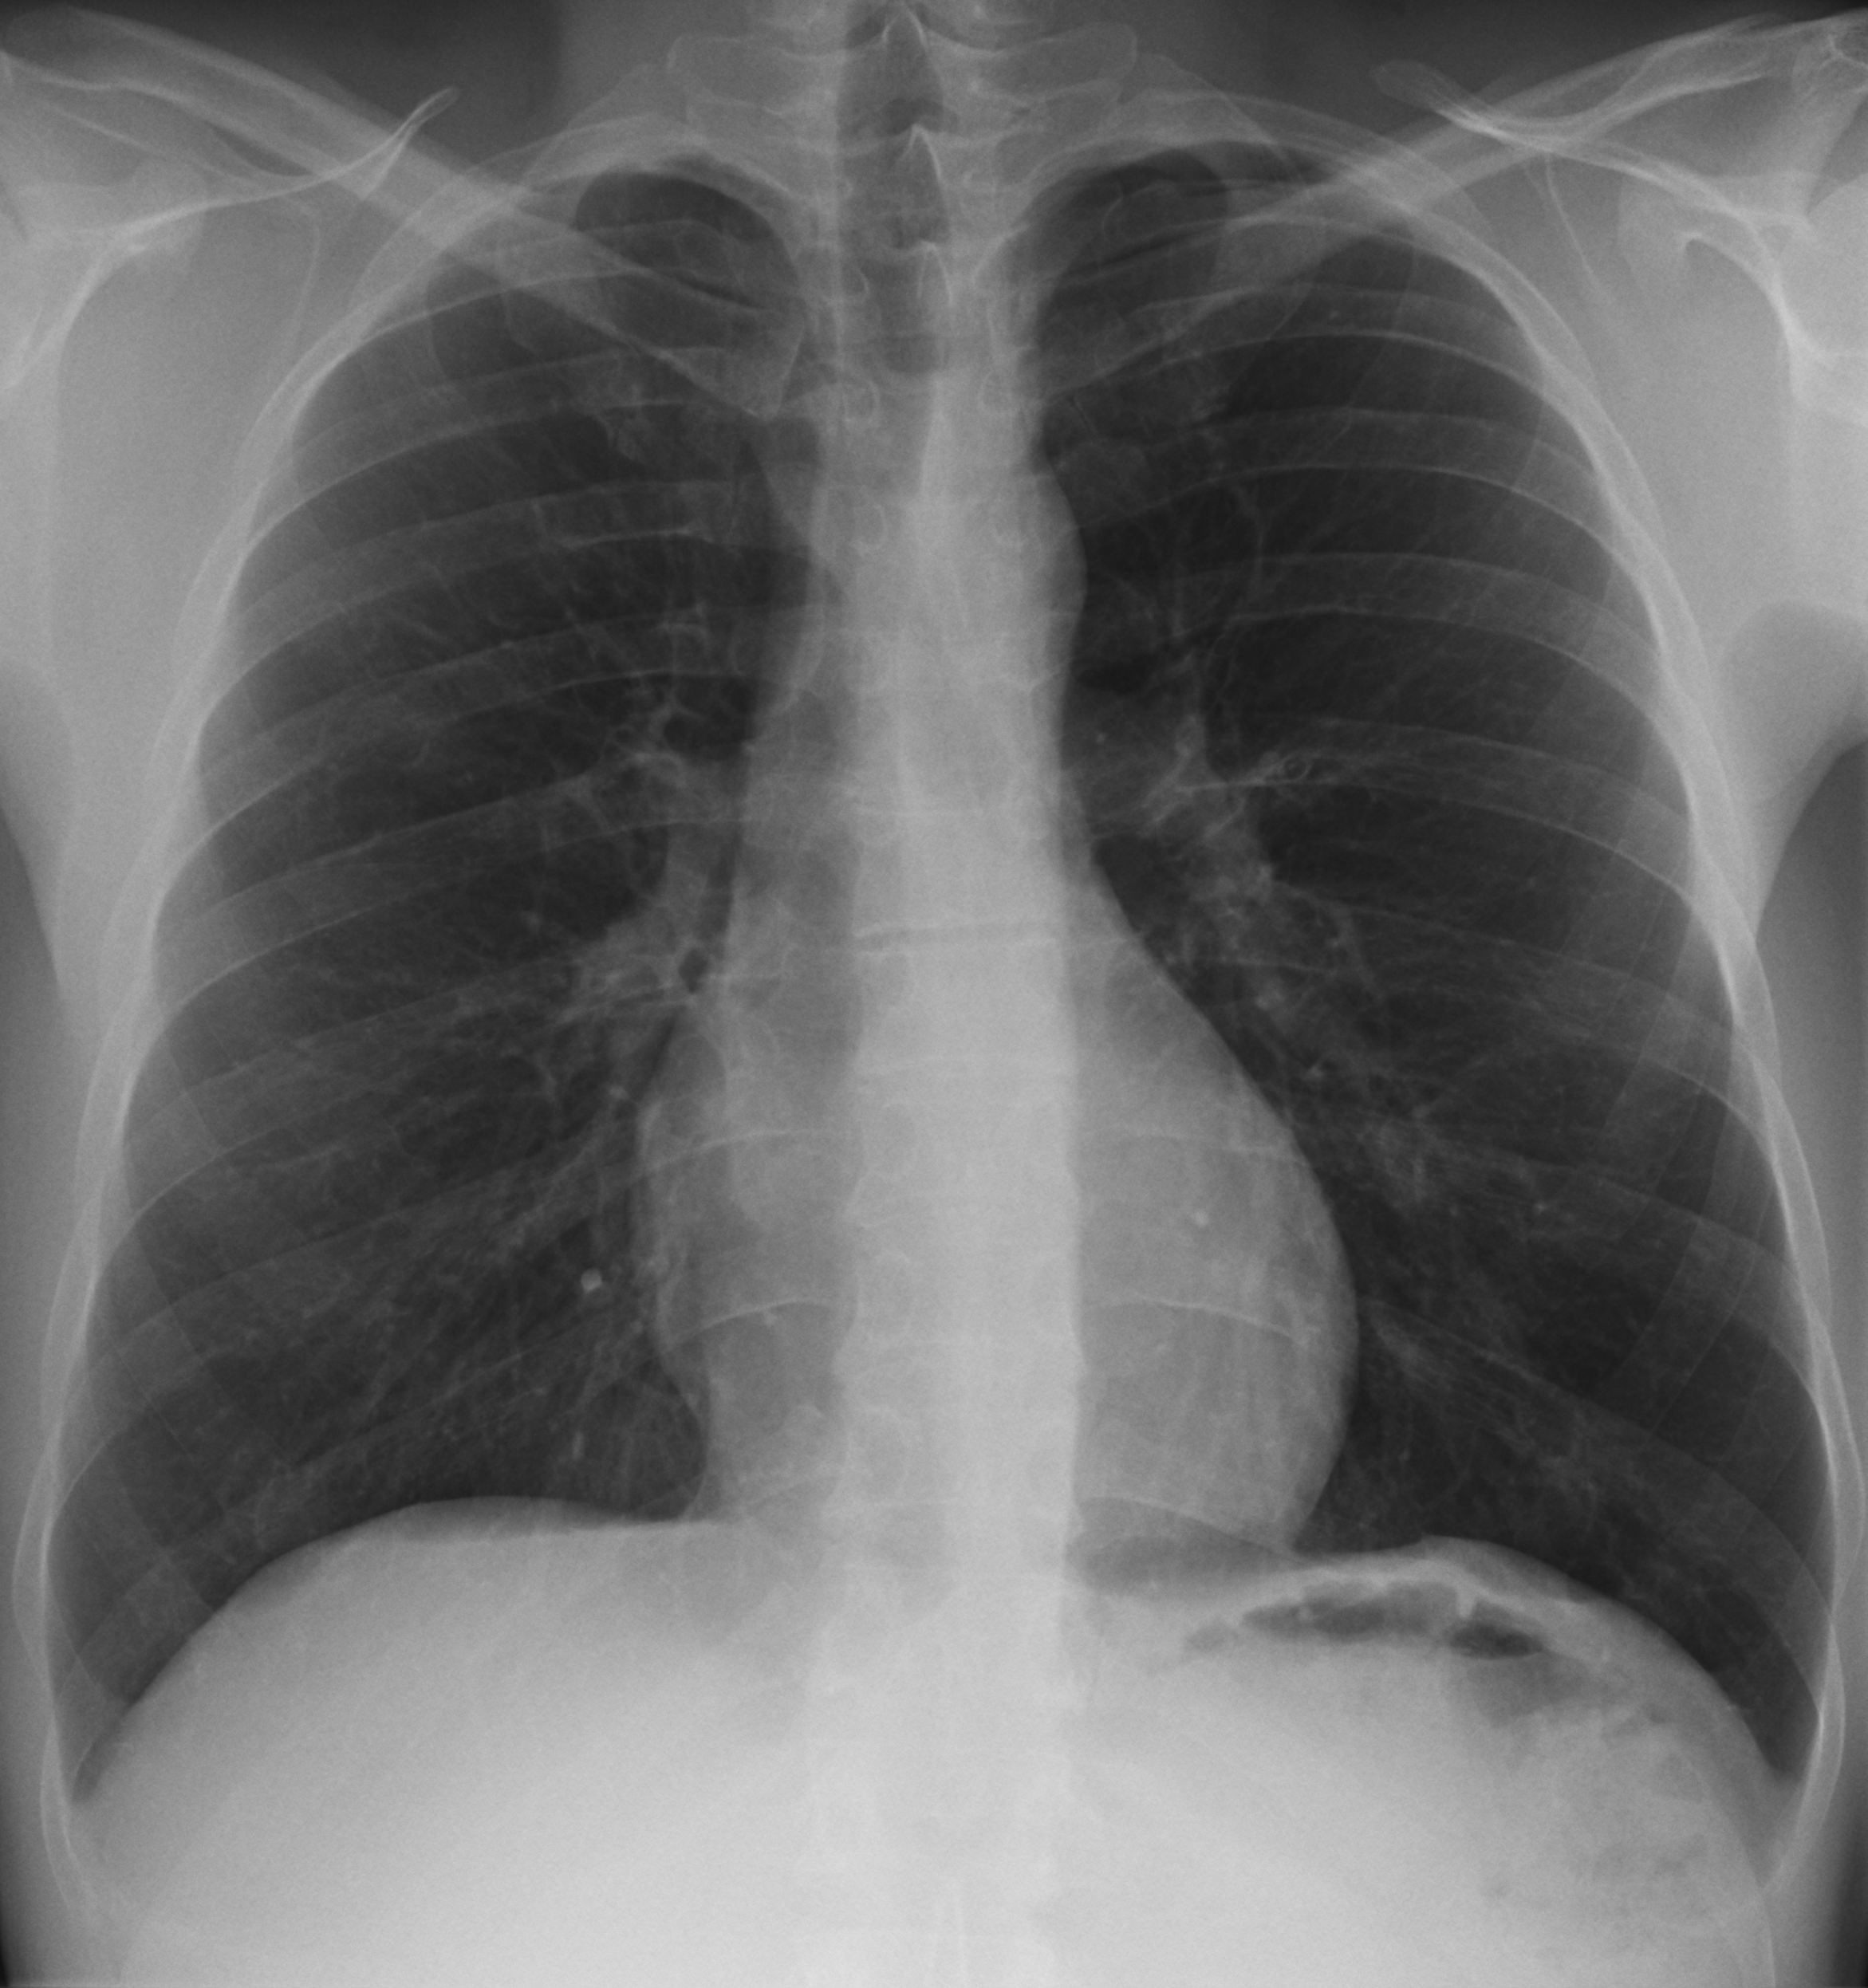

Two datasets DS1 and DS2 were constructed using extracted data from the above two data repositories for training and testing proposed model and other pre-trained models. DS1 includes about 150 CXR of Covid-19 and 150 CXR of normal subjects which was designed for binary classification problem. DS2 was designed for three class classification where we differentiate Covid-19 infected subjects from normal and other pneumonia type infections. This dataset consists of 150 Covid-19, 150 other pneumonia and another 150 instances for normal CXR images. Within the samples of other pneumonia CXR, there are cases of bacterial infections, fungal infections and other viral infections of subjects. Figure 1 presents representative CXR images for Covid-19, bacterial, fungal, other viral and normal patients respectively.

\zihao-5Fig. 1: \zihao-5Representative CXR images from datasets corresponding to different infections

In these sample CXR images, there are certain areas with hazy opacification or increased attenuating as these areas are filled with some substances other than air. This is an indication of displacement of air by fluid and a collapse of periphery of lungs due to various infections. Though these areas are visible as more grey and cloudy compared to darker areas with lower attenuation, differentiating the cause of infection is not possible for human eye alone. Further, the specific radiographic patterns can be variable depending on different viral strains making it hard even for expert to diagnose using CXR alone. This further implies the demand for efficient and accurate automated CXR based techniques for disease diagnosis.